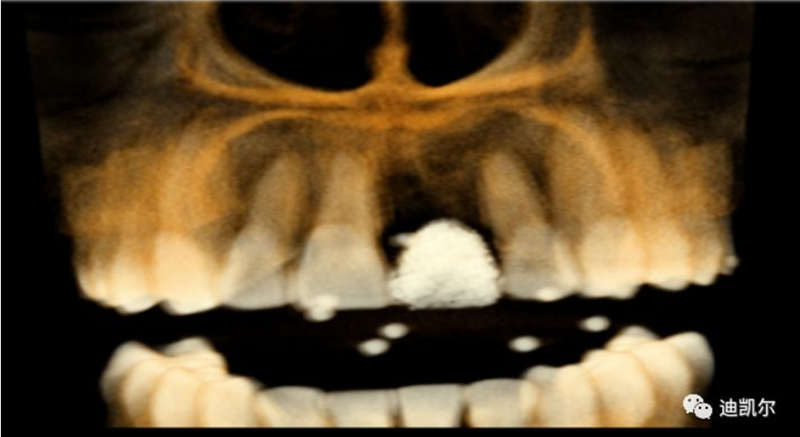

術(shù)前CBCT圖像和測量數(shù)據(jù)

*CBCT顯示骨缺損嚴重,種植窩洞制備困難,種植體很難獲得初期穩(wěn)定性

患者佩戴此U型管開合拍攝CBCT,其中可以獲得缺牙區(qū)修復(fù)體的切端及齦緣等信息

患者佩戴此U型管開合拍攝CBCT,U型管中的放射標記點清晰顯影